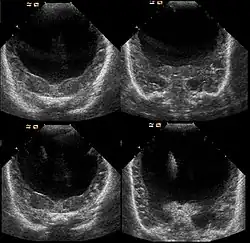

Die Diagnose kann vorgeburtlich im Rahmen von Pränataldiagnostik durch insbesondere Feinultraschalluntersuchungen im zweiten Trimenon, teils aber auch schon früher, gestellt werden. Während die Feststellung der alobären und der semilobären Form oft recht einfach ist, ist die der lobären Holoprosencephalie komplizierter.

Nachgeburtlich sind die Schnittbildverfahren Sonographie und Magnetresonanztomographie Methoden der Wahl.[19]